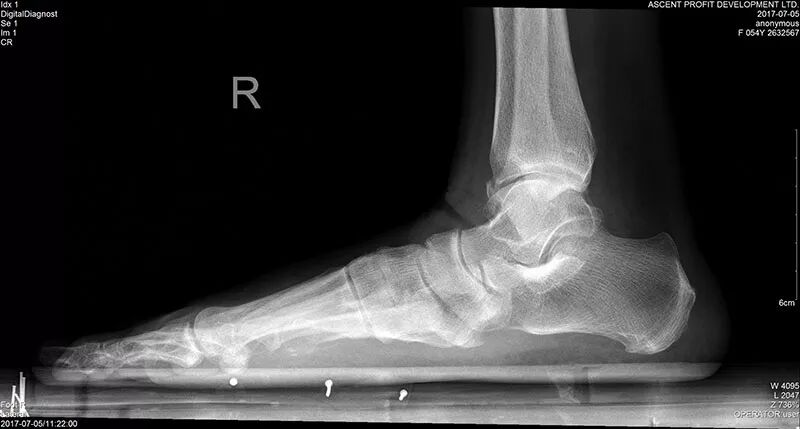

今年54岁的李老师曾经是一位中学英语老师,她自小就是“平足”。所谓平足,就是脚底整个是平的,从内侧面看,没有一个弓形的弧度。

在去过N家医院试过N种治疗方法无效后,她找到了苗旭东主任。经检查,李老师的平足,因为常年的站立、穿高跟鞋等因素,已经发展成了“平足症”,她的胫后肌腱(维持足弓形态和足内翻动作的主要动力肌腱)已经断裂,跟骨外翻,需要做矫形手术。